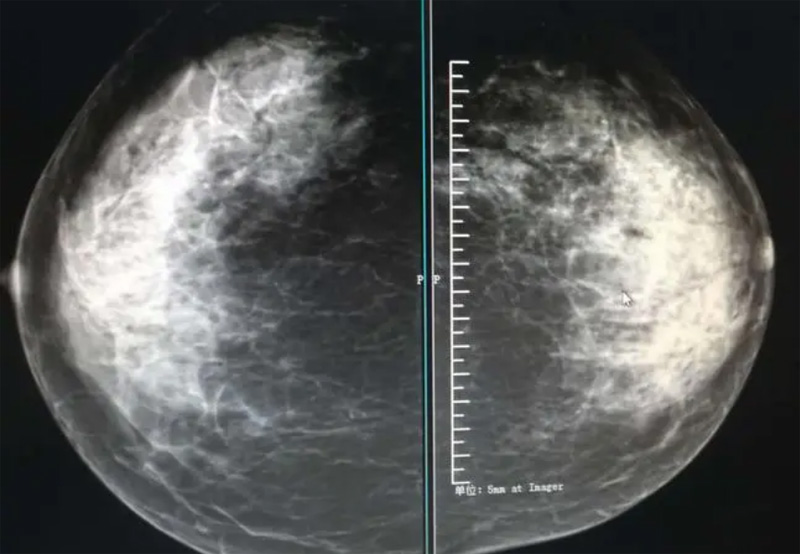

乳腺DR攝影體位有頭尾位及內(nèi)外側(cè)斜位,

乳房在片子的中央,乳頭切線位,可見(jiàn)小部分胸大肌,內(nèi)側(cè)乳腺組織應(yīng)全部包括在片中,外側(cè)乳腺組織盡可能包括在片中。一張好的MLO位圖像顯示如下:乳房被推向前上,乳腺實(shí)質(zhì)充分展開(kāi),胸大肌可見(jiàn),較松弛,下緣達(dá)到乳頭水平,乳頭在切線位,部分腹壁包括在片中,但與下部乳腺分開(kāi),絕大部分乳腺實(shí)質(zhì)顯示在片中。乳腺組織外緣可見(jiàn)乳頭的輪廓;乳腺后方的脂肪組織被很好地顯示出來(lái),乳房無(wú)皺褶。對(duì)于CC位及MLO位顯示不良或未包全的乳腺實(shí)質(zhì),可以根據(jù)病灶位置的不同選擇以下體位:外內(nèi)側(cè)位(LM)、內(nèi)外側(cè)位(ML)、內(nèi)側(cè)頭尾軸位(MCC)、外側(cè)頭尾軸位(LCC),尾葉位(CLEO)及乳溝位。在臨床實(shí)踐中,對(duì)于常規(guī)體位上發(fā)現(xiàn)的異常改變,可以進(jìn)一步采取一些特殊的攝影技術(shù),包括局部加壓攝影、放大攝影或局部加壓放大攝影技術(shù)。

2、規(guī)范觀圖程序:屏幕軟閱讀或在專(zhuān)用日光觀片燈下膠片閱讀,后者應(yīng)同時(shí)準(zhǔn)備白熾強(qiáng)光燈及觀片放大鏡。注意雙側(cè)乳腺配對(duì)觀察,推薦雙眼橫向掃描,進(jìn)行雙乳相同部位圖像比較分析。

3、乳腺實(shí)質(zhì)背景的確定:觀察乳腺實(shí)質(zhì)與脂肪的構(gòu)成比例,了解乳腺實(shí)質(zhì)類(lèi)型,以判斷對(duì)某些乳腺攝影征象敏感性的影響,有利于確定乳腺攝影對(duì)疾病的診斷價(jià)值。